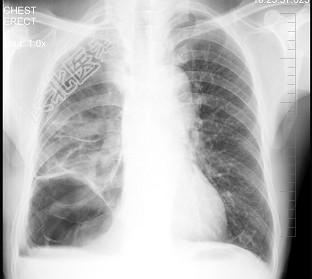

- 单项选择题男性患者,62岁, 常感胸闷、气逼,X线检查如图, 最可能的诊断是 ( )

A、右侧肺大疱

B、右侧气胸

C、右侧肺脓肿

D、右侧胸膜肥厚

E、气胸